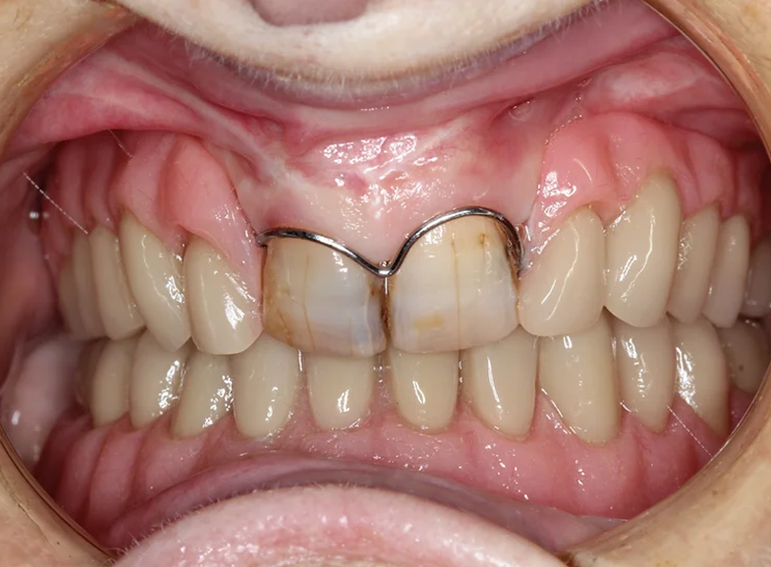

Upper and lower dentures (with implants) after broken jaws.